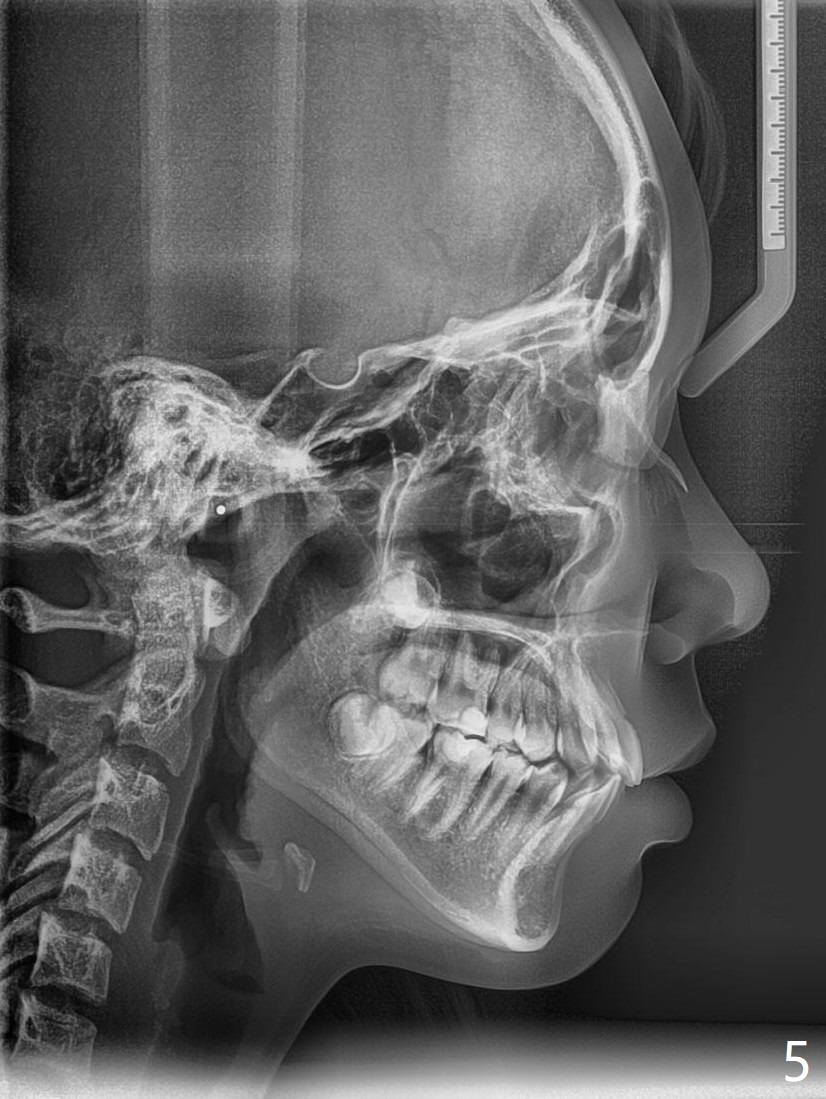

A 14-year-old woman, used to be a dental phobic (Fig.13), agrees with orthodontic treatment. Her mother is concerned about UL1 protrusion (Fig.8,11) and decalcification (Fig.8 *) and UR4 cross bite (Fig.7,10,14). There is mild lip constraint (Fig.1,3), as related to light dental protrusion (Fig.2,4), although the upper dental midline is not deviated (Fig.2). History shows that UR3 erupts before UR D is extracted, which is associated with UR4 cross bite. After arch expansion, consider proximal reduction to reduce anterior overjet if present. In fact that latter is not done; instead Class II is conducted.